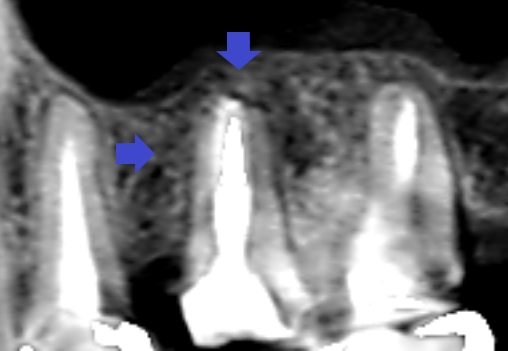

精密再根管治療6ヶ月後の口蓋根の矢状断のCT画像です。根の先端から横にかけてできていた長い影が消失し、歯槽骨が再生しています(青い矢印)。